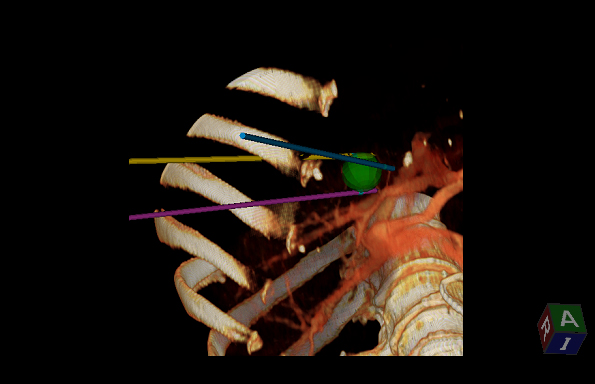

Aplicación: Abdomen

Función/análisis: 3D Sim-Navigator

Comentarios: Hígado